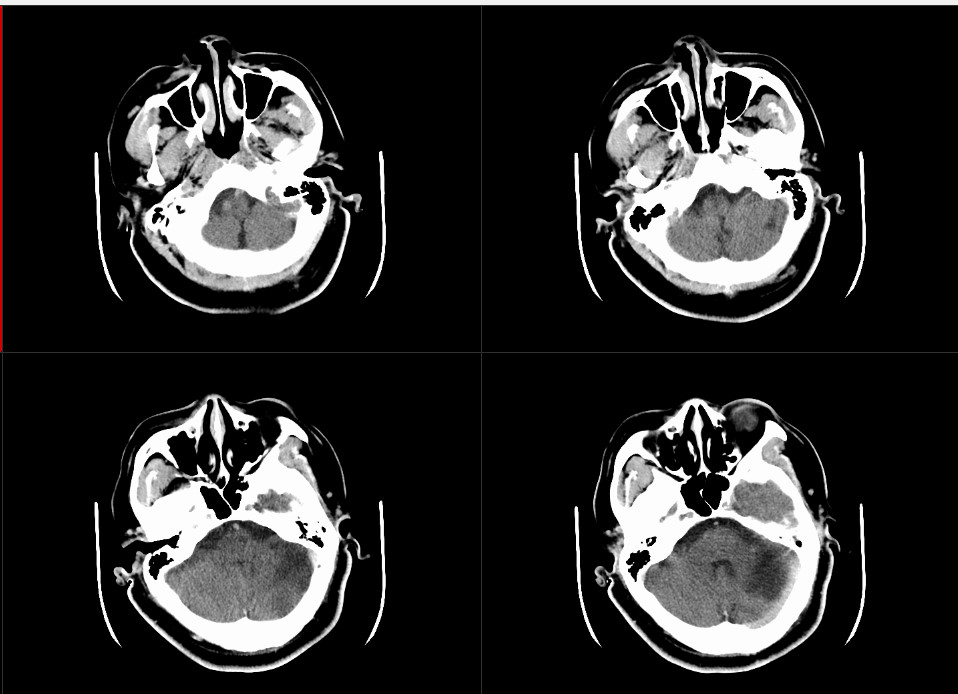

像老林遭遇的中風,也稱缺血性腦卒中,大多由動脈硬化、血管狹窄等引起,可是檢查顯示,老林的腦血管都長挺好,看起來沒問題,那有沒有可能是心源性疾病導致的?這也是引起中風的常見病因。

巧的是,術後老林在NICU時,護士在監視器上捕捉到了一個異常信號:房顫。雖然這個信號一閃而過,後來也沒有再出現過,卻在發生的那個瞬間被護士一眼捕捉到。

另外,中風病人都會做TCD發泡試驗,正常來說,從手臂靜脈打入的微小氣泡,不應該出現在腦血管裏。但是,醫生在老林的腦血管里發現了氣泡。

「這說明他的左心房和右心房之間可能存在空隙,也就是卵圓孔未閉。」

隨後,醫生為老林安排了動態心電圖和經食道心臟彩超,結果證實,房顫和卵圓孔未閉,通通都有!

這就是典型的心源性中風,「發病在心、傷害在腦」,因為有房顫,心房跳動紊亂,容易長血栓;因為卵圓孔未閉,血栓容易通過卵圓孔進入左心和體循環,引起中風。buff疊加,中風風險直線升高!